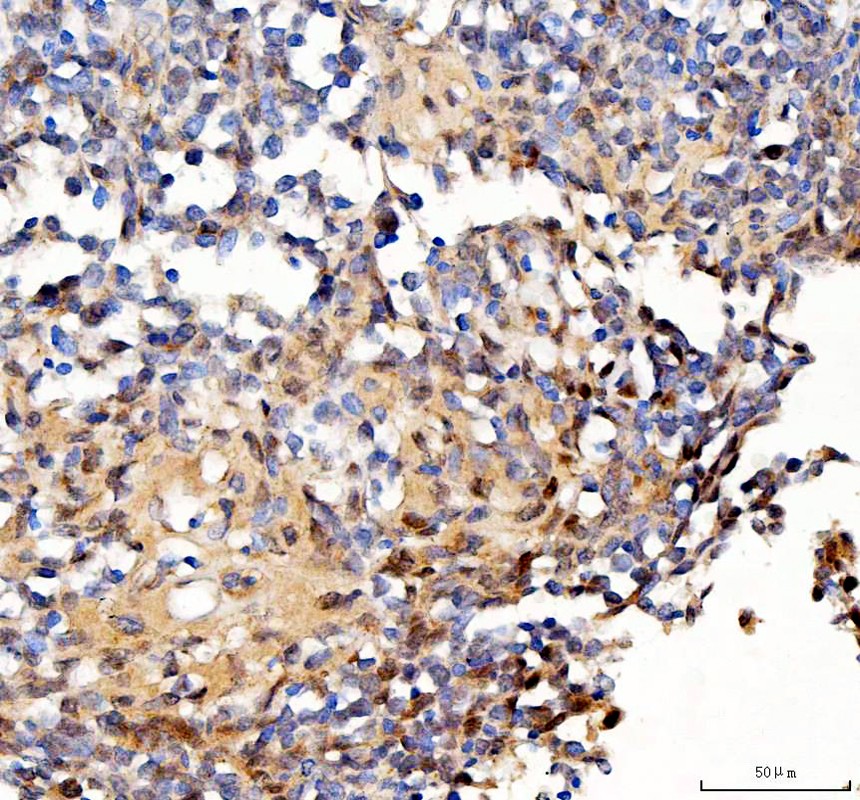

IHC analysis of Survivin/BIRC5 using anti-Survivin/BIRC5 antibody (A00379).

Survivin/BIRC5 was detected in a paraffin-embedded section of human lymphoma tissue. The tissue section was incubated with rabbit anti-Survivin/BIRC5 Antibody (A00379) at a dilution of 1:200 and developed using HRP Conjugated Rabbit IgG Super Vision Assay Kit (Catalog # SV0002) with DAB (Catalog # AR1027) as the chromogen.